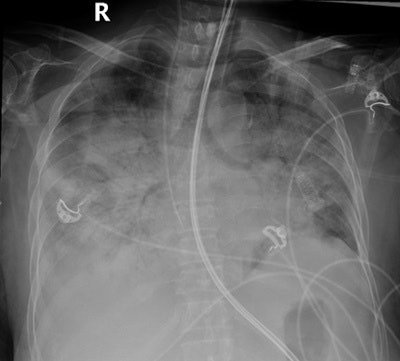

In the paper published online on 21 March 2016 and scheduled to appear in the June edition of the American Journal of Roentgenology (June 2016, Vol. 206:6, pp. 1-9), the authors also described how quantitative evaluation of sequential chest x-rays in severely ill patients in the intensive care unit (ICU) can be used to predict a poor prognosis and higher mortality in MERS-CoV patients.

The mean chest radiographic score was significantly higher in patients who died than in those who recovered (13.0 ± 2.6 versus 5.8 ± 5.6, p = 0.001). Furthermore, a higher association rate of the following features was seen in patients who died than in those who recovered: pleural effusion (63% versus 14%, p = 0.001), type 4 radiographic progression (63% versus 6%, p = 0.001), and pneumothorax (47% versus 0%, p = 0.001), according to the authors. They stressed the need for careful and early identification of these prognostic chest x-ray findings in MERS-CoV-infected patients.

"The presence of type 4 radiographic deterioration pattern, pleural effusion, and pneumothorax were predictors of imminent danger requiring most active intervention and treatment," Das said in an interview.